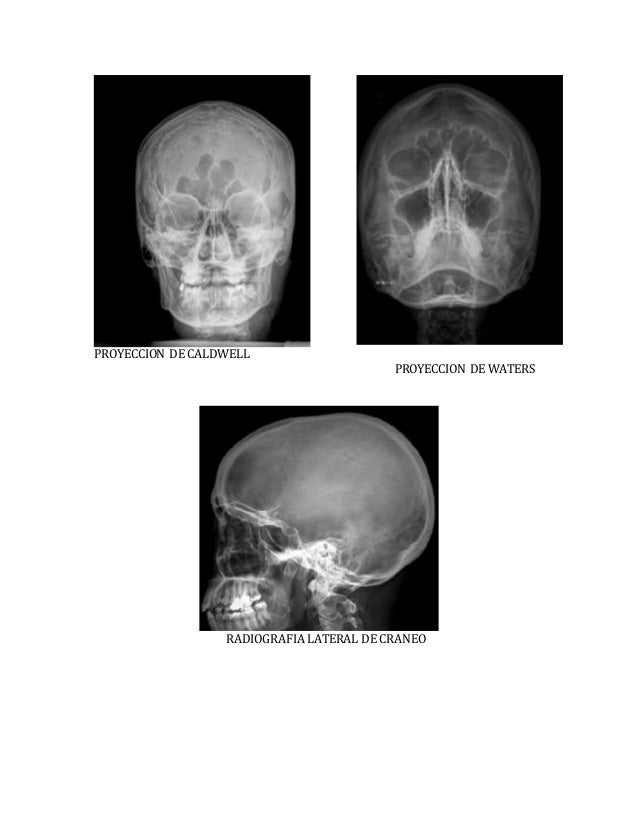

Dx por imagen Craneo Columna RADIOGRAFIA DE CRANEO Proyección de Waters, esta proyección nos

RADIO ANATOMIA CRANEO

Caldwell, Towne YouTube

Incidencias de CADWELL y WATERS NeuroMedicine uDocz